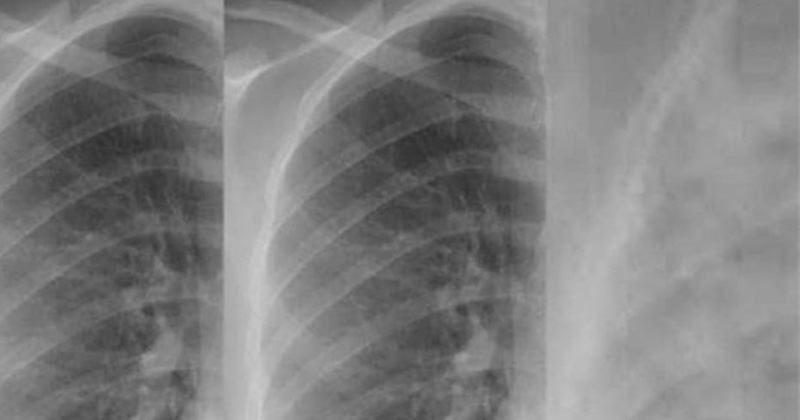

Doctora comparte imágenes de la afectación pulmonar en vacunados y no vacunados

Compartió una foto comparativa de rayos X realizados a pacientes que han superado el Covid-19, mostrando cómo afecta los pulmones en quienes no se vacunaron.